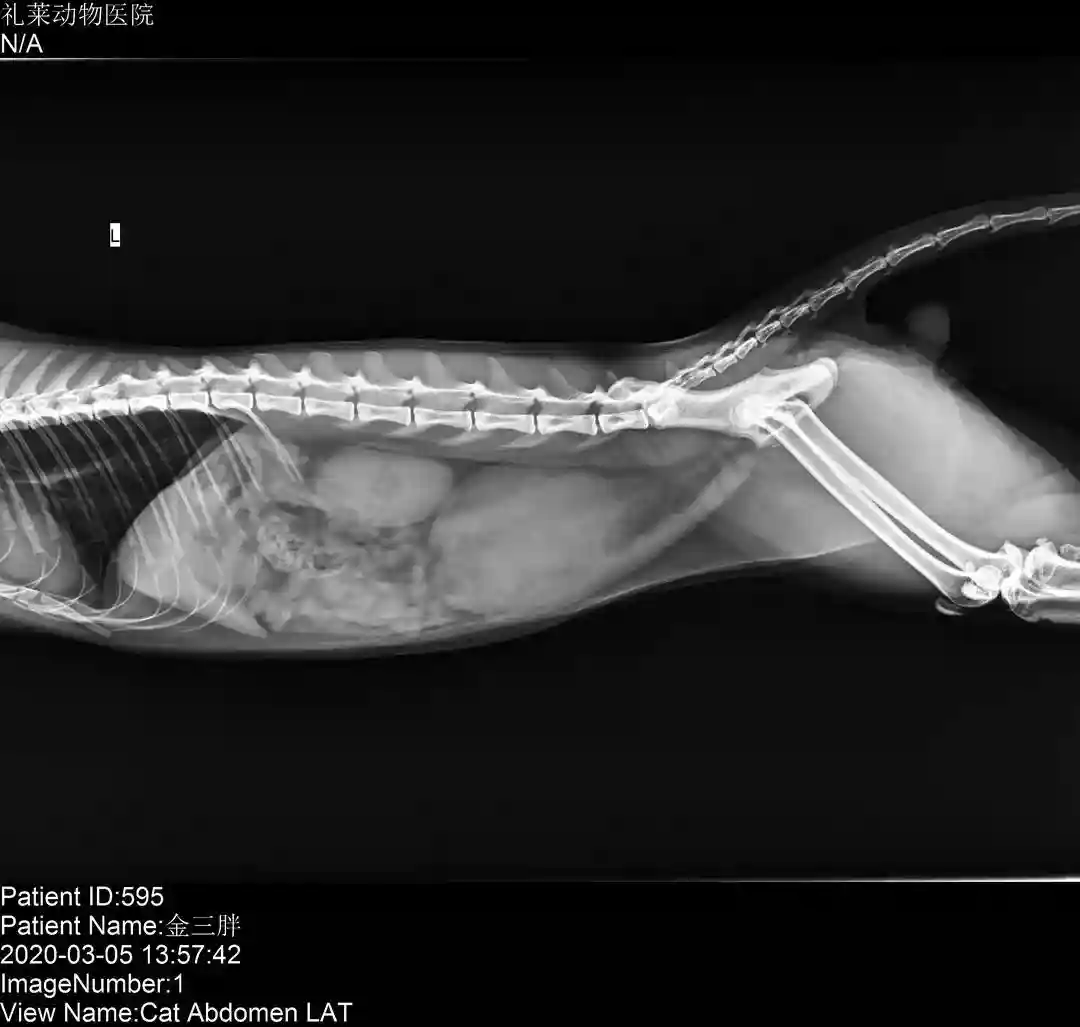

DR:

DR显示膀胱积尿较多,膀胱膨大,其他暂未见异常。